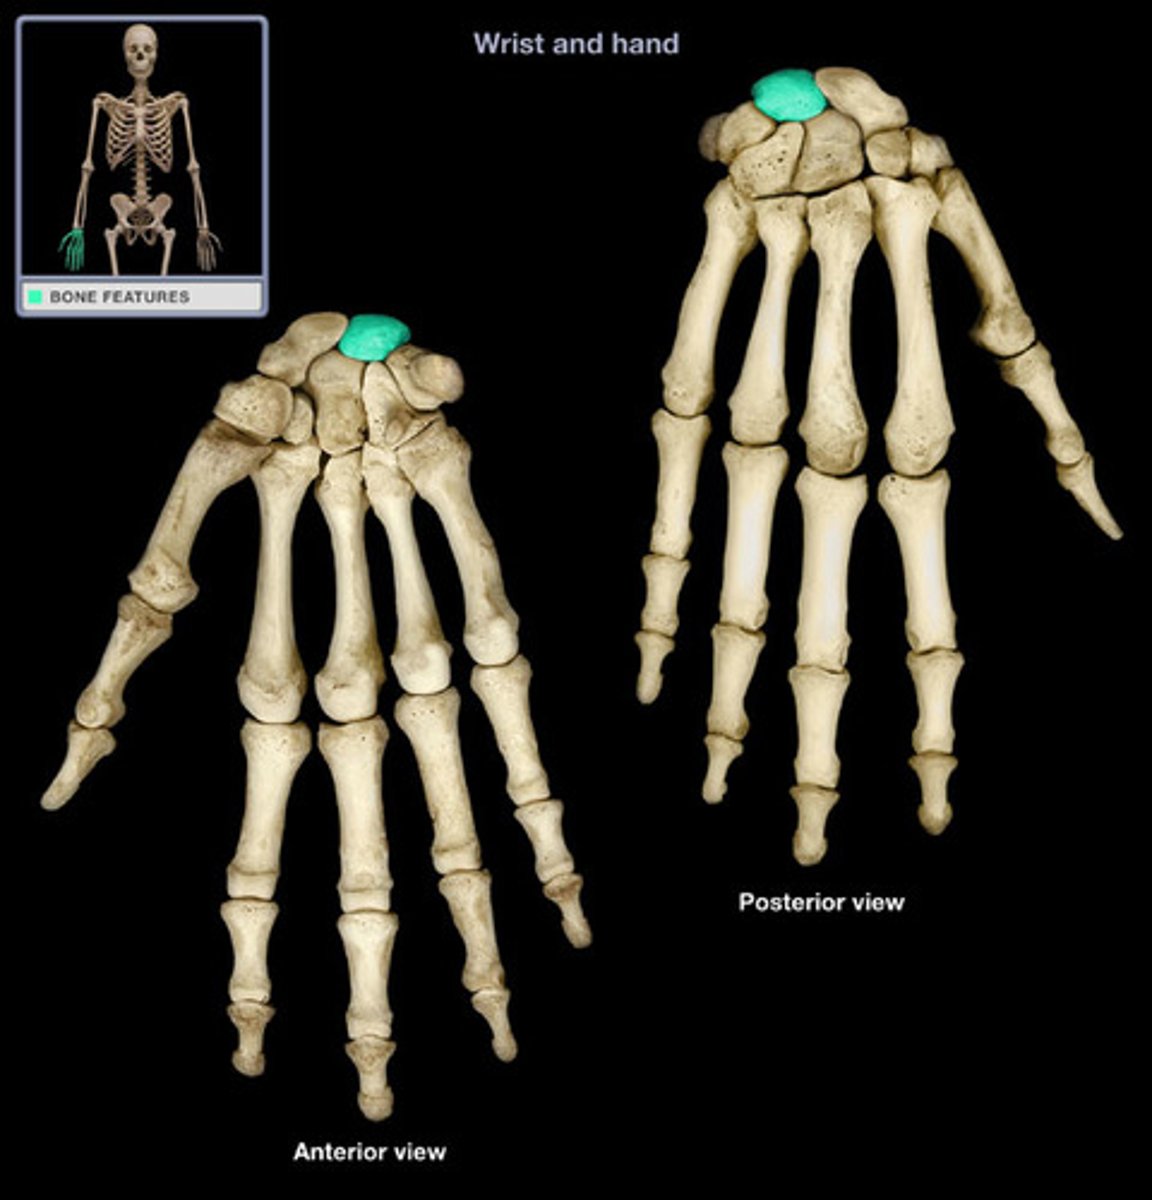

Carpal bones

scaphoid, lunate, triquetrum, pisiform, trapezium, trapezoid, capitate, hamate

Scaphoid

Name this specific bone of the hand.

Lunate

Name this specific bone of the hand.

Triquetrum

Name this specific bone of the hand.

Pisiform

Name this specific bone of the hand.

Trapezium

Name this specific bone of the hand.

Trapezoid

Name this specific bone of the hand.

Capitate

Name this specific bone of the hand.

Hamate

Name this specific bone of the hand.